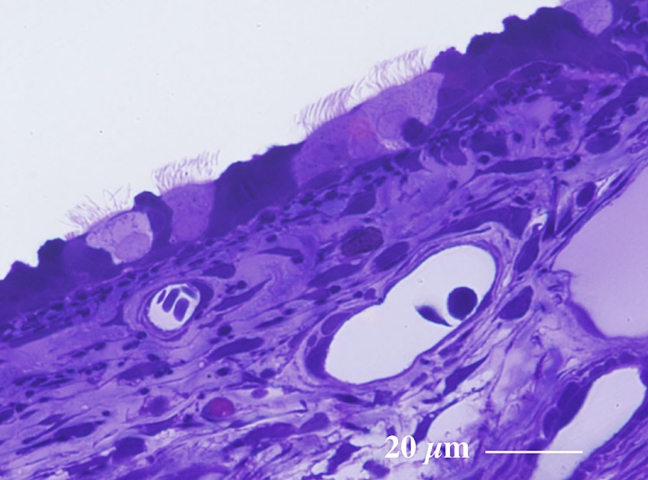

気 管(ラット) Trachea ( rat )

厚さ1 µm エポン樹脂準超薄切片のトルイジンブルー染色光学顕微鏡画像

Light microscopic image of 1 µm-semithin epoxy resin section with toluidin-blue staining

気管には粒子状物質の排除に関与する線毛細胞 ciliated cell が観察されます。

(エポン樹脂包埋準超薄切片のトルイジンブルー染色光顕像)